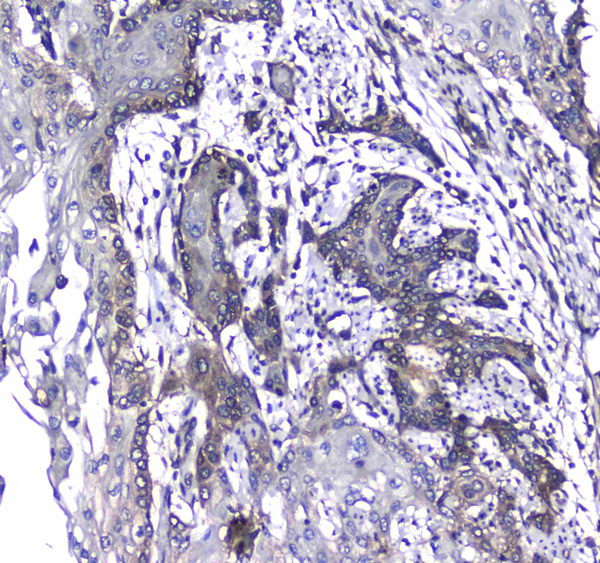

Survivin, Monoclonal Antibody (Cat# AAA25268)